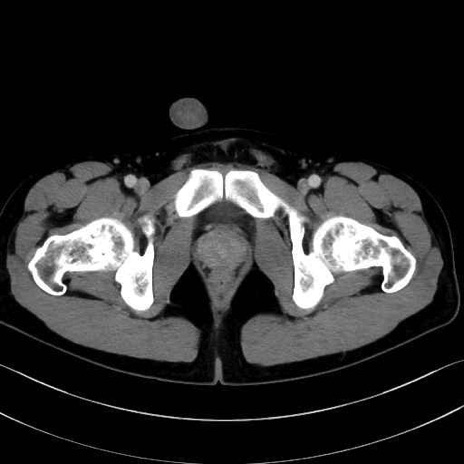

小殿筋 (Gluteus minimus)